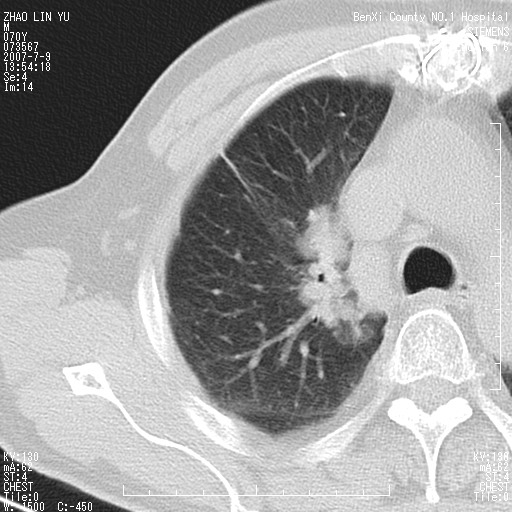

以下是引用王靖旗在2007-7-10 17:12:00的发言:[br] 男、70、咳嗽两个月,半年前换瓣手术,胸片未见异常,于昨天行x片发现右肺上野大片影,行ct扫描,这里是减薄图像,余肺正常。明天晚上会有增强扫描片,到时我会上传。[br][br] 冠状位请大家细看,应该是有意义的,[br][br] 请大家先看平扫发表意见。[br][br]

以下是引用zhangzhongshou在2007-7-10 21:43:00的发言:[br]右肺上叶周围型肺癌,以孤立型细支气管肺泡癌可能性大。